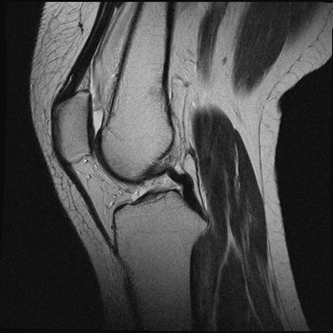

四肢・関節MRI検査

靭帯損傷や骨折など、関節病変の診断をするために行う検査です。また、軟部腫瘤の検査も行うことができます。